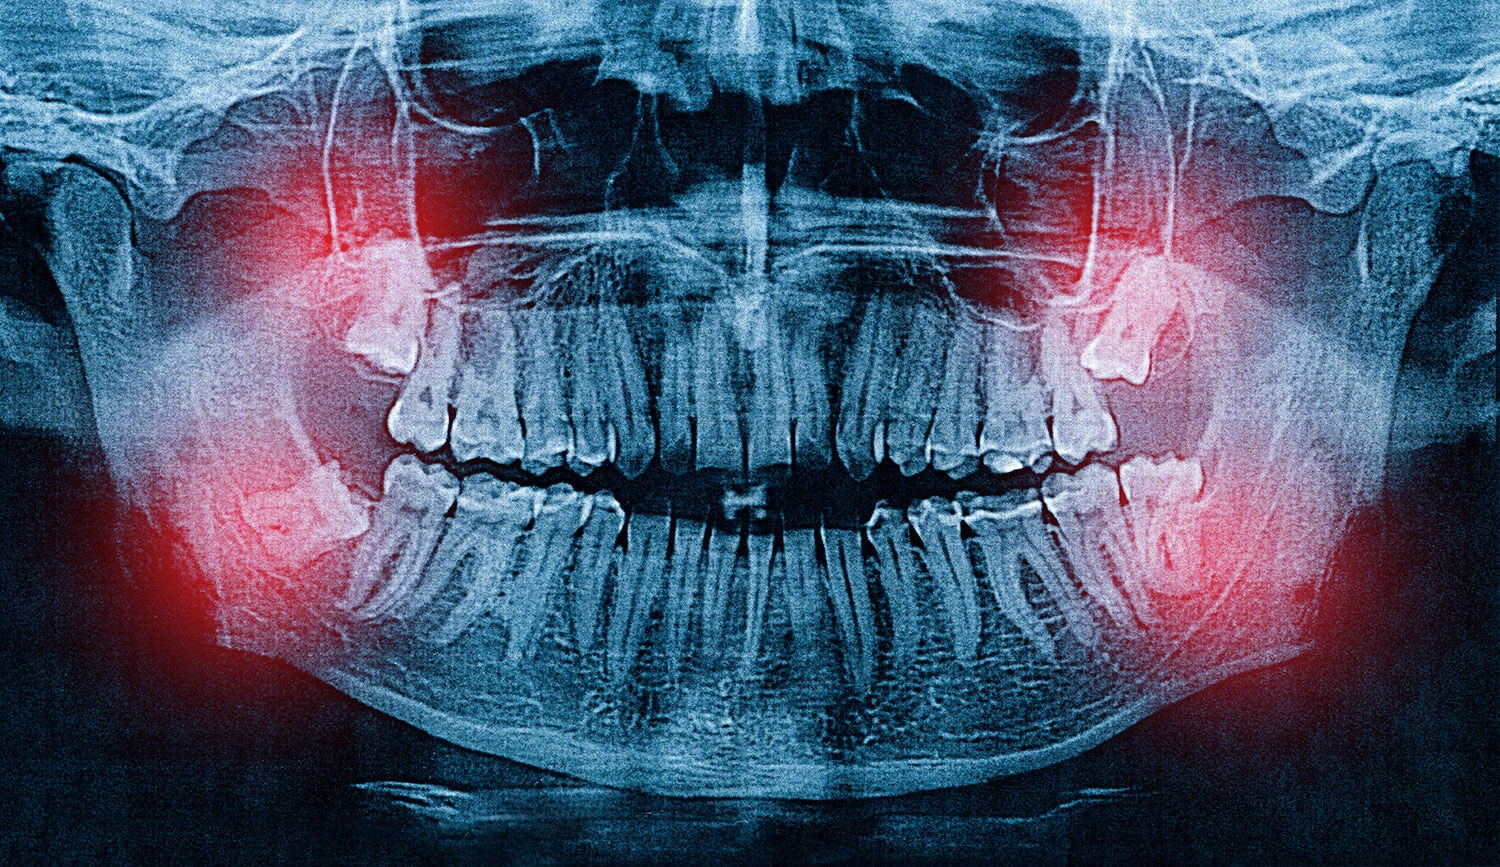

Wisdom teeth, also known as third molars, usually erupt between the ages of 17 and 25. While some people experience no problems, many face issues like pain, infection, or teeth crowding due to impacted wisdom teeth. At AMD Dental Clinic, Jaipur, we often treat patients who are worried about whether wisdom teeth can push their other teeth out of alignment.

Impacted Wisdom Teeth: Teeth trapped in the gums or jawbone.

Angled Eruption: Growing sideways and pushing against nearby teeth.

Partial Eruption: Teeth breaking through the gums only partially, making them prone to infection.

One of the most common concerns patients share at AMD Dental Clinic is whether wisdom teeth can shift their other teeth. The answer is yes, indirectly. Here’s how:

As wisdom teeth push forward, they can crowd the front teeth, especially the lower incisors. This is why some people notice crooked teeth after wisdom tooth eruption.Pressure on Jaw & Gums

Impacted wisdom teeth exert constant pressure on surrounding teeth, causing discomfort and gradual misalignment.Bite and Jaw Pain

Advanced Technology: Digital X-rays and 3D scans for accurate diagnosis.